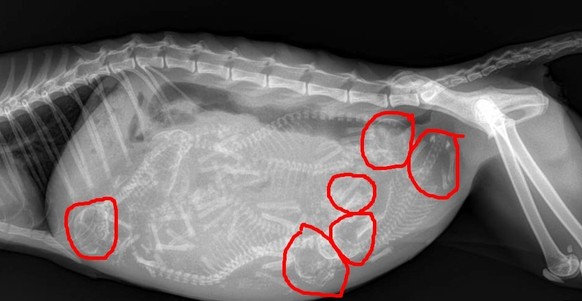

Wie viele Katzenbabys zählst du?

Gemäss der Person, die das Foto zu Verfügung gestellt hat, sind es sechs.